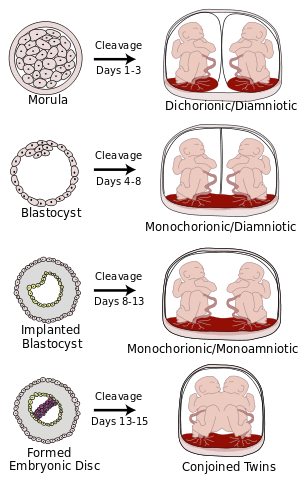

Monochorionic twins are monozygotic (identical) twins that share the same placenta. If the placenta is shared by more than two twins (see multiple birth), these are monochorionic multiples. Monochorionic twins occur in 0.3% of all pregnancies.[1] 75% of monozygotic twin pregnancies are monochorionic; the remaining 25% are dichorionic diamniotic.[2] If the placenta divides, this takes place after the third day after fertilization.[2]

Monochorionic twins generally have two amniotic sacs (called Monochorionic-Diamniotic "MoDi"), but sometimes, in the case of monoamniotic twins (Monochorionic-Monoamniotic "MoMo"), they also share the same amniotic sac. Monoamniotic twins occur when the split takes place after the ninth day after fertilization.[2] Monoamniotic twins are always monozygotic (identical twins).[3] Monochorionic-Diamniotic twins are almost always monozygotic, with a few exceptions where the blastocysts have fused.[2]